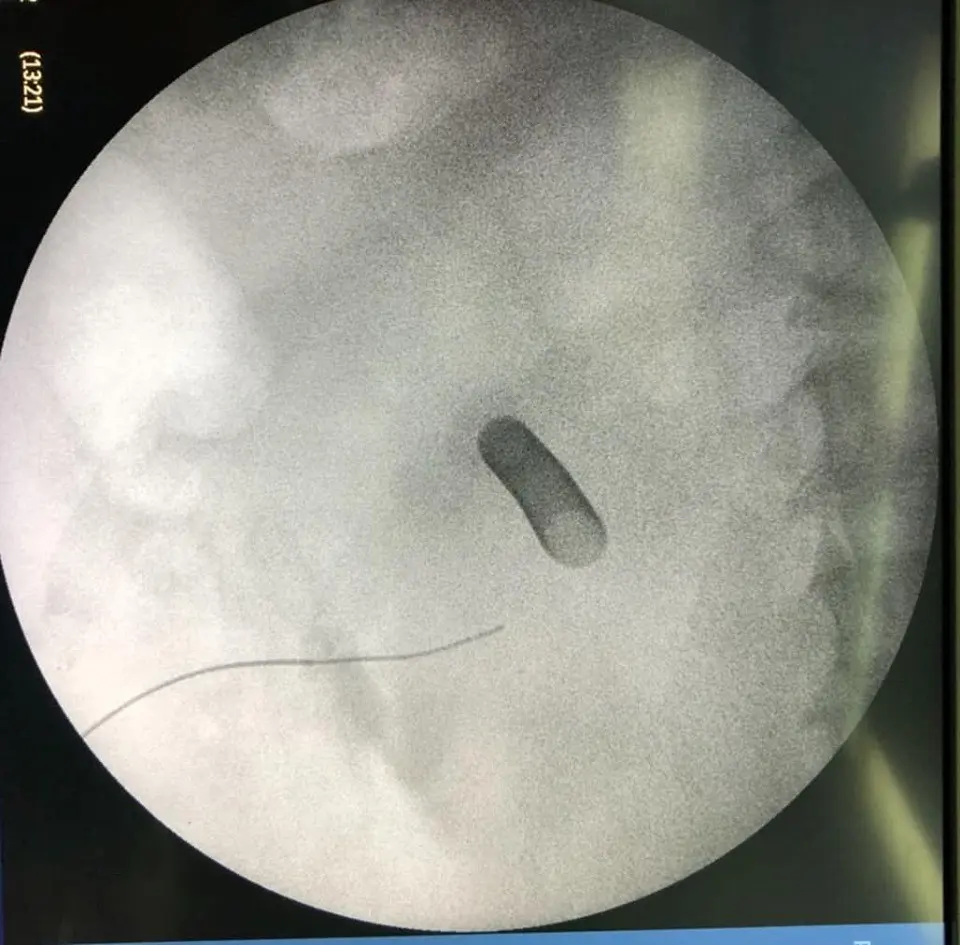

ตะลึง! กองนิ่วที่ผ่าตัดจากคนไข้รายเดียว!!

กองนิ่วที่ได้รับการผ่าตัดจากคนไข้รายเดียว หลังจากที่คนไข้รายนี้ต้องทนทุกข์ทรมานจากอาการปวดหลังและไตเสื่อม สุดตะลึง! เมื่อเข้ารับการผ่าตัดพบว่านิ่วเยอะมาก! จนสามารถนำมาเรียงให้เป็นคำว่านิ่วได้เลย

โดยภาพนี้ถูกโพสท์มาจากเฟซบุ๊กคุณ Sirianan Prasit คุณหมอที่โรงพยาบาลยะลา โดยได้โพสท์ข้อความระบุว่า ของกลางที่พบในคนไข้รายหนึ่ง หลังจากที่ต้องทนทุกข์ทรมานกับอาการปวดหลังและอาการไตเสื่อม

คงไม่ต้องบอกว่า......คืออะไร 😁😁😁 ไม่อยากเป็นนิ่ว โปรดดื่มน้ำวันละ6-8แก้วต่อวันครับ นิ่วในไตใหญ่เบ้อเริ่ม

Uro Yala Team